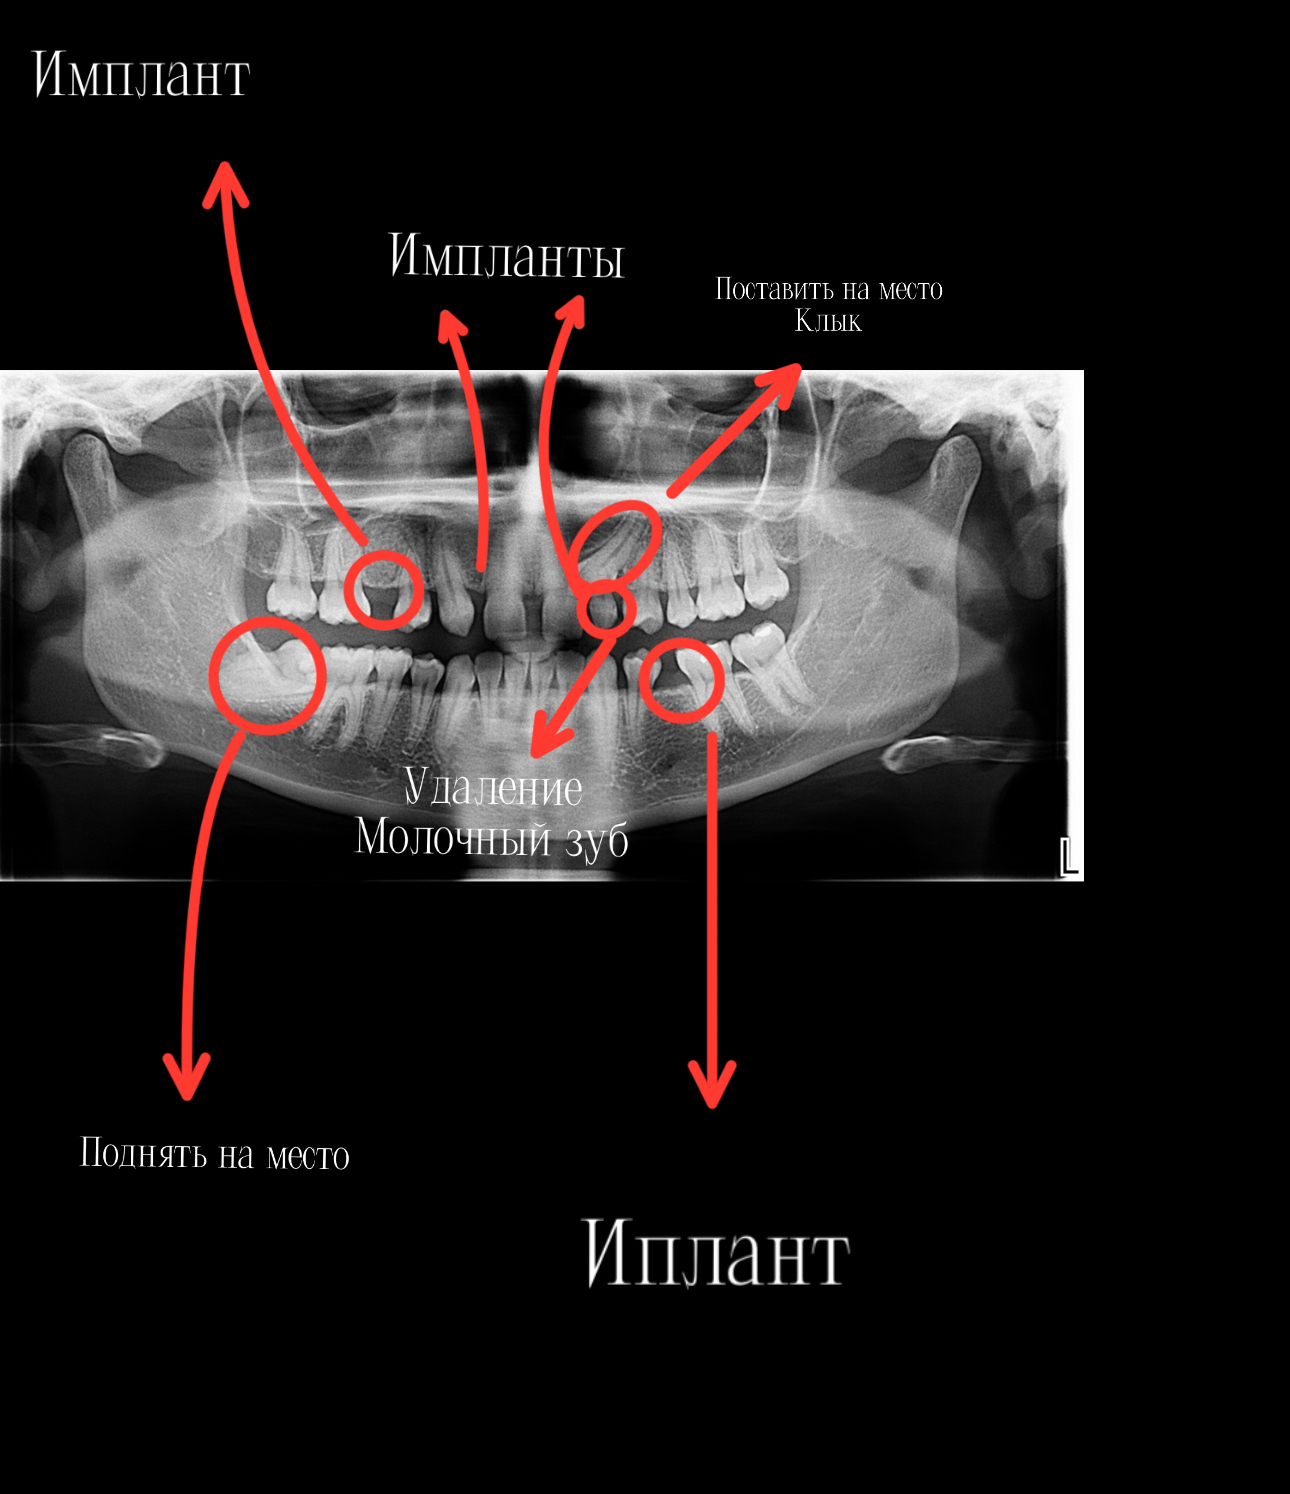

На один из приемов,врач заметила,что что-то не так с зубами и направила меня на снимок всей челюсти (ОПТГ),там было выявлено,что нет зачатков зубов,а именно 2х боковых резцов и 2х вторых премоляров. В итоге мы имеем - адентию.

Впереди долгий путь на котором меня ждет еще установка 4х имплантатов.

На данном этапе мне установили минивинт и поднимают нижний второй моляр.

Полную картину зубов я прикреплю ниже.